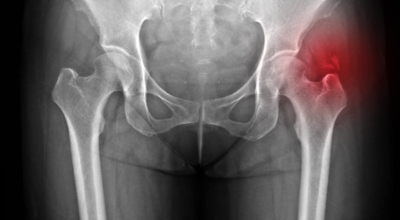

각별히 젊은 남성분들에게 잘 발생하며 엉덩이와 골반 주위에 뻐근한 통증이 동반되며 정상적인 보행이 되지 않고 절뚝거리는 증상이 나타난다면 대퇴골두 무혈성 괴사일 가능성이 있습니다. 이 증상은 괴사 부위의 골절이 발생되어 고관절 훼손으로 이어지면 생기는 증상으로 아직까지 정확한 원인은 규명하기 힘드나 과음이나 고지혈증, 스테로이드 과남용이 영향을 줄 수 있답니다.